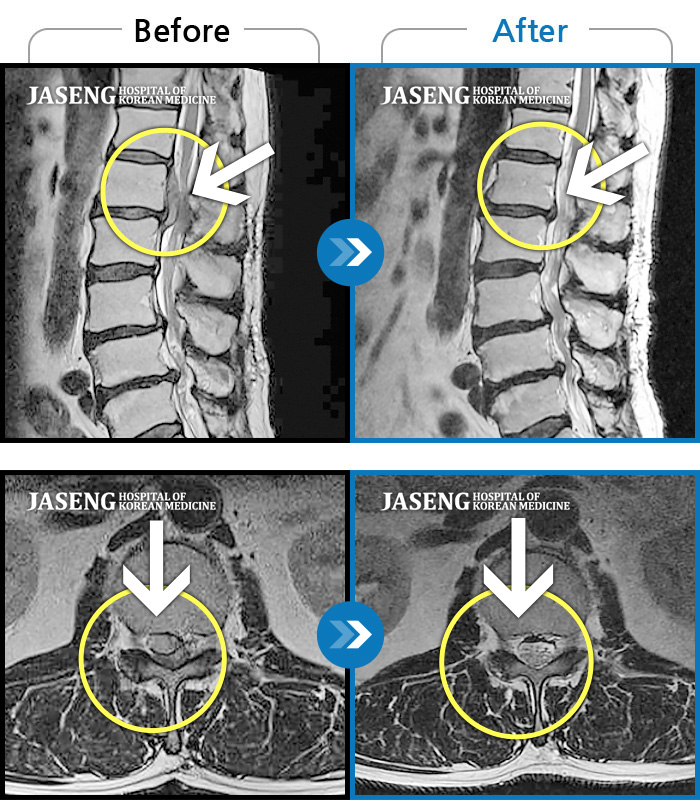

허리디스크

수원 · 김태성 원장

허리 통증과 좌측 대퇴부~종아리 저림과 통증

촬영시기

2011.03.14 ~ 2024.05.24

2024.11.21